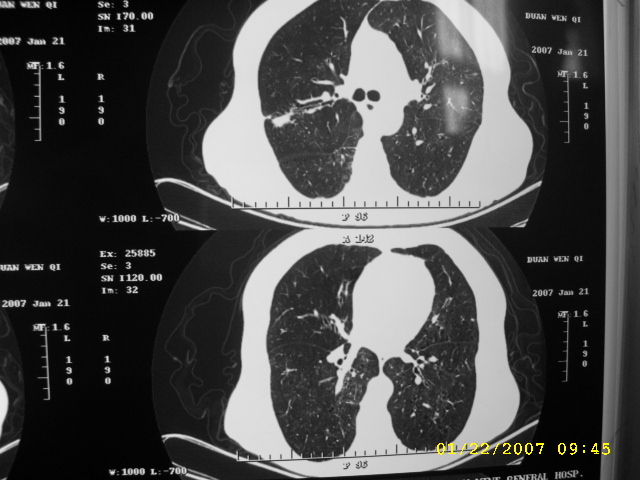

女,75.胸痛。

07.01.21.

明显的不规则形肿块,分叶、短毛刺、胸膜刺激征,血管扭曲征等周围型肺癌的征象明显,应首先考虑周围型肺癌。应与肺多发结核球相鉴别

双侧肺内块状病灶,均见分叶毛刺,左肺见典型胸膜凹陷,双侧双原发癌.

1.双肺上叶及右肺下叶结节,周围散在卫星灶,接近4年的病史,纵隔无肿大淋巴结,考虑结核

2.桶状胸,慢支,肺气肿